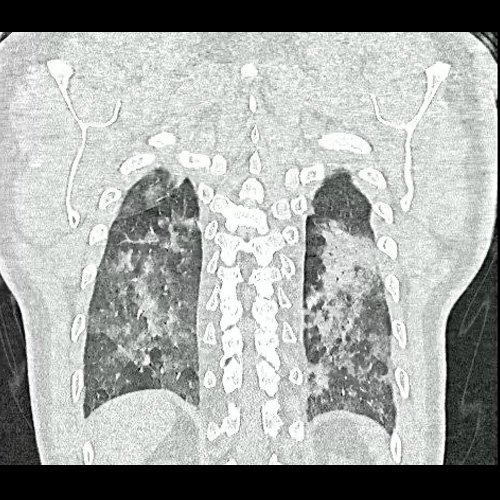

Tomografia de torax sin contraste endovenosos (Ventana pulmonar- Corte coronal)

• Tomografía de tórax sin contraste endovenoso (Dia 0):Se observan múltiples áreas de consolidación parenquimatosa con broncograma aéreo y de distribución difusa por ambos pulmones, predominando en los lóbulos inferiores, asociadas a engrosamiento de los septos y rodeadas de tenue vidrio esmerilado. Se identifican estructuras ganglionares lateroaórticas, pretraqueales y subcarinales, ninguna de ellas sin alcanzar rango megálico.